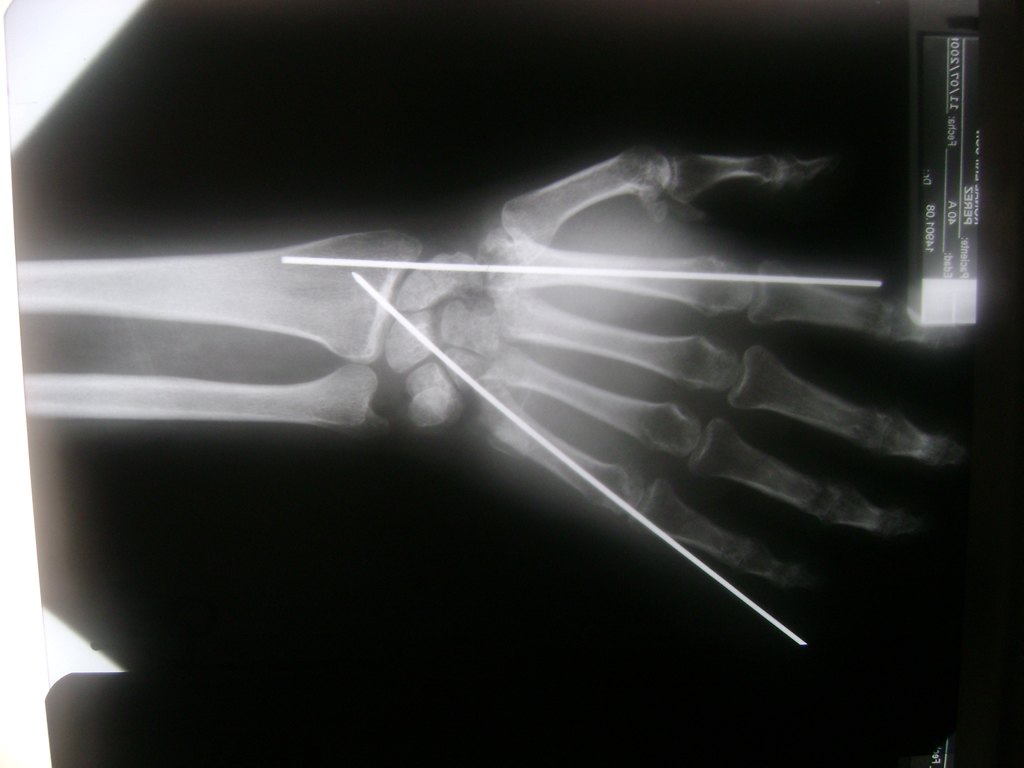

Cirugías de Húmero - Cirugías de Muñecas y Manos

Los procedimientos más comunes en cirugía de la mano son aquellos destinados a reparar traumatismos, incluyendo lesiones de tendones, nervios, vasos sanguíneos, y articulaciones; huesos fracturados; y quemaduras, cortes, y otros daños de la piel.